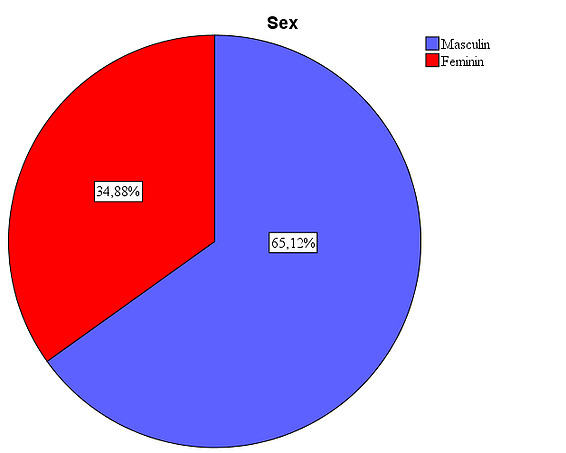

The studied sample includes subjects of both sexes, with males accounting for 55.6% and females accounting for 44.4%.

We observe that we have a negative asymmetric curve, slightly tilted to the right (Skewness coefficient -0.252), with more extreme values to the left and platykurtic (Skewness coefficient -0.892), flatter than a normal distribution, with more values dispersed over a larger interval around the mean. The explanation for this distribution is given by a higher number of eye traumas that are more common in the male population compared to the female population, who opted for surgical intervention most frequently to improve the cosmetic appearance.

Figure 1: Gender distribution in the study. The presence of a larger number of male patients is due to the large number of eviscerations after ocular trauma, a pathology more frequently encountered in males (33 cases). The implant types were used in a relatively equal proportion: in 26.7% of patients the silicone implant was used, in 25.6% the synthetic hydroxyapatite implant, in 24.4% the acrylic implant, and in 23.3% the natural hydroxyapatite implant.

- The studied sample includes subjects of both sexes, with males accounting for 55.6%, while females accounting for 44.4%, explained by the high rate of ocular trauma in male patients

- The studied sample includes subjects of both sexes, in relatively equal proportions, male representatives being in the proportion of 52.3%, while female representatives in the proportion of 47.7%, a proportion explained by the high rate of surgical interventions post-traumatic, more common in the male population.

Objective of the study: Aging leads to laxity of orbital tissues and fat that contributes to the etiology of many eyelid conditions such as ectropion, entropion, dermatochalasis or blepharoptosis. These changes can affect the position of the eyelids, eyeball or eyebrows and surgical interventions can contribute to the final cosmetic appearance especially after evisceration and prosthetics of the anophthalmic cavity. Tyers and Collin first described in 1982 the insufficient cavity syndrome characterized by a deep superior sulcus, enophthalmic appearance, ptosis of the upper eyelid and malposition of the lower eyelid, which can occur especially in the case of cavities insufficiently filled by prosthetics 2. Through this study, I want to make a comparison between the 2 types of implants regarding the existence of aesthetic differences between the prosthetic eye and the healthy eye 4 years after the prosthesis, the existence of aesthetic differences between the prosthetic eye with an acrylic implant and the one with a hydroxyapatite implant 4 years after the prosthesis and the existence of a correlation between age and the aesthetic appearance of the prosthetic eye 4 years after the prosthesis. The present paper presents a clinical, cohort, retrospective, non-randomized, comparative study analyzing patients undergoing evisceration between January 2006 and December 2010. The surgical approach was followed by the implantation in the anophthalmic cavity of a coralline hydroxyapatite implant or a non-integrated implant (PMMA). Investigated population The present study considered a sample of 43 subjects with ocular implants. The descriptive characteristics of the sample are presented below: Gender Analyzing the structure of the sample according to the sex of the subjects, it is observed that men have a share of 65.1%, while women represent only 34.9%.

Figure 7: Gender distribution of the sample: , it is observed that men have a share of 65.1%, while women represent only 34.9%. Age: Looking at the sample from the perspective of the subjects’ age, it is found that their average age is 57.42. The age deviates from the average by plus or minus 5.36 years. The modal value (Mode) shows us that the age of 58 was the most common among the people in the sample.